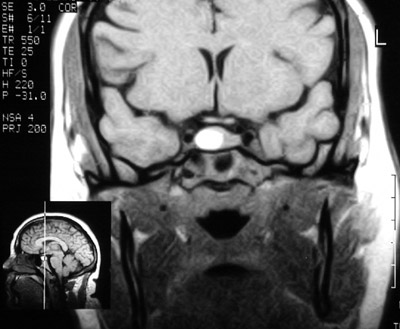

This enhanced MRI scan in coronal view demonstrates a brightly enhancing microadenoma of the pituitary which was manifested by prolactin secretion and not mass effect.